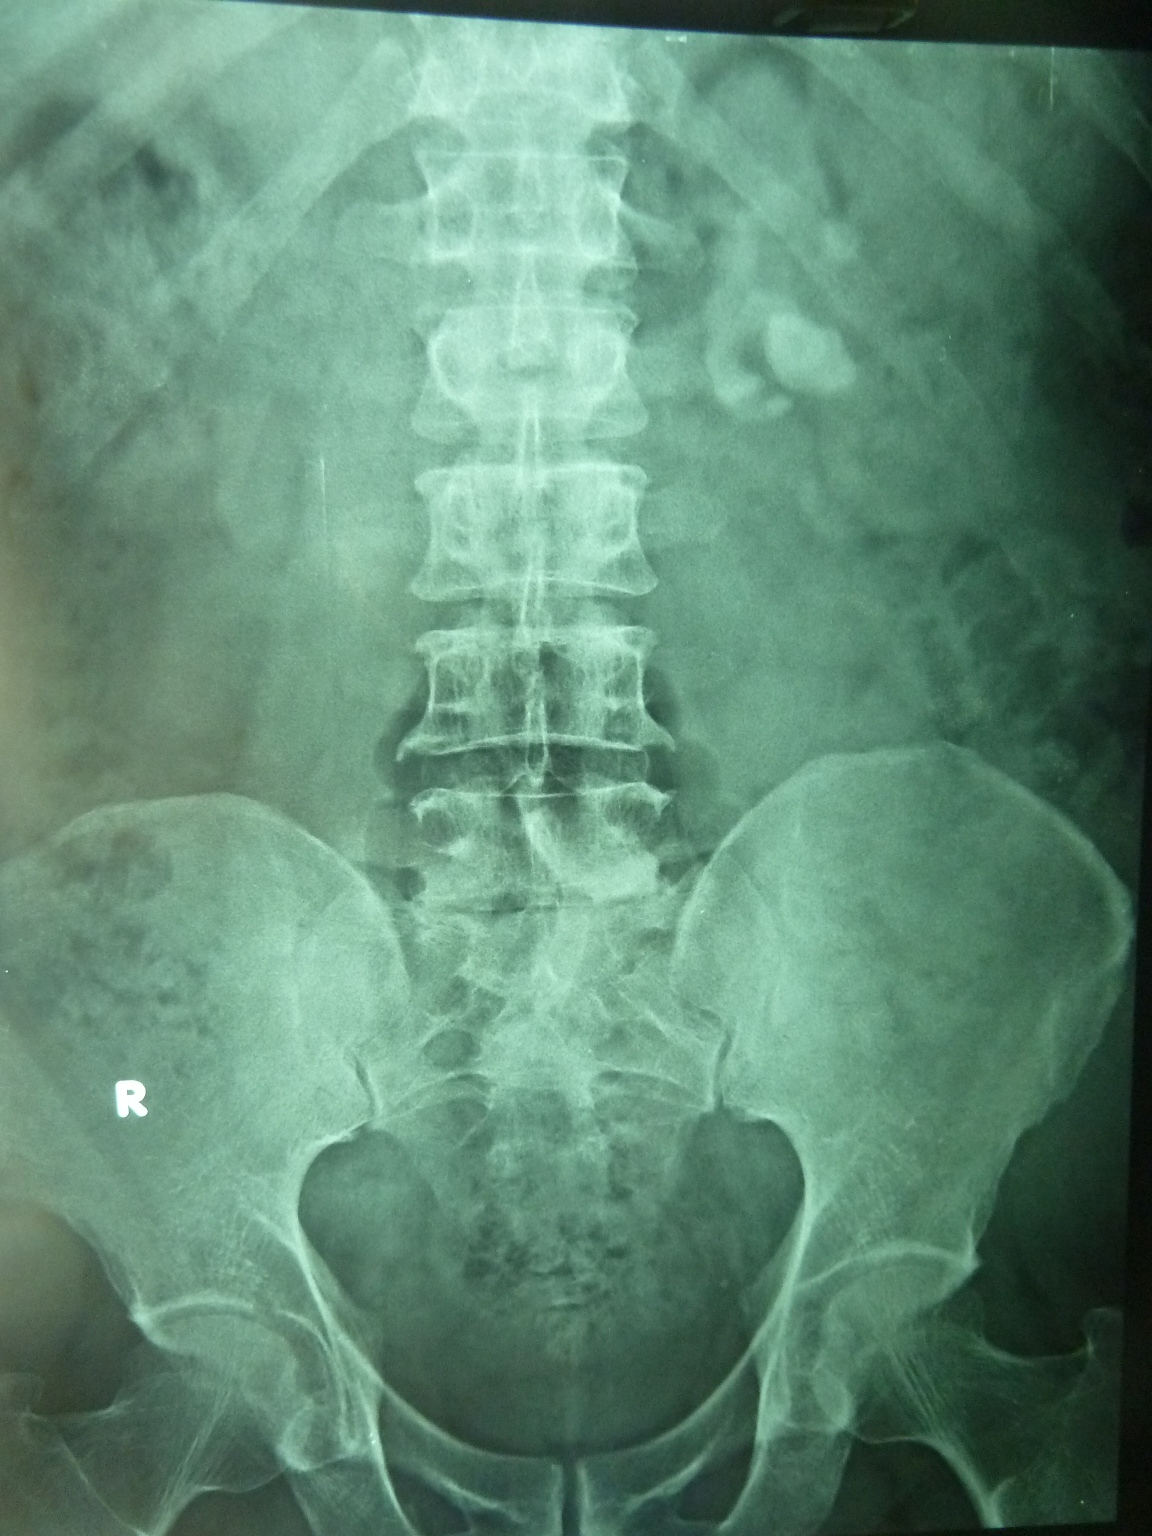

Archive Of Unremarkable Radiological Studies Abdominal XRay (KUB) Stepwards What Is An Us Kub Kub ultrasonography is a diagnostic tool that utilizes sound waves and a computer to generate images of kidneys, ureters and urinary bladder. Renal ultrasound scans, which people may also call kidney. Kub ultrasound is a test of the kidneys, ureters, and bladder. If you analyse a body diagram, you will find the kidneys on the backside of the. Ultrasound is. What Is An Us Kub.

Interpreting An Abdominal XRay (KUB) Stepwards What Is An Us Kub Ultrasound is a test that uses sound waves to create an image of the inside of your body. Renal ultrasound scans, which people may also call kidney. A kidney and bladder ultrasound, or renal ultrasound, uses high frequency sound waves transmitted through a transducer (probe) to. Kub ultrasound is a test of the kidneys, ureters, and bladder. Kub ultrasonography is. What Is An Us Kub.

Interpreting An Abdominal XRay (KUB) Stepwards What Is An Us Kub What to know about kidney ultrasound scans. Ultrasound is a test that uses sound waves to create an image of the inside of your body. Renal ultrasound scans, which people may also call kidney. Kub ultrasound is a test of the kidneys, ureters, and bladder. A kidney and bladder ultrasound, or renal ultrasound, uses high frequency sound waves transmitted through. What Is An Us Kub.

Xray KUB showing 2 calculi overlying the sacrum in the Openi What Is An Us Kub In medicine, kub refers to a diagnostic medical imaging technique of the abdomen and stands for kidneys, ureters, and bladder, although in fact the ureters only show if they are. If you analyse a body diagram, you will find the kidneys on the backside of the. What to know about kidney ultrasound scans. Ultrasound is a test that uses sound. What Is An Us Kub.